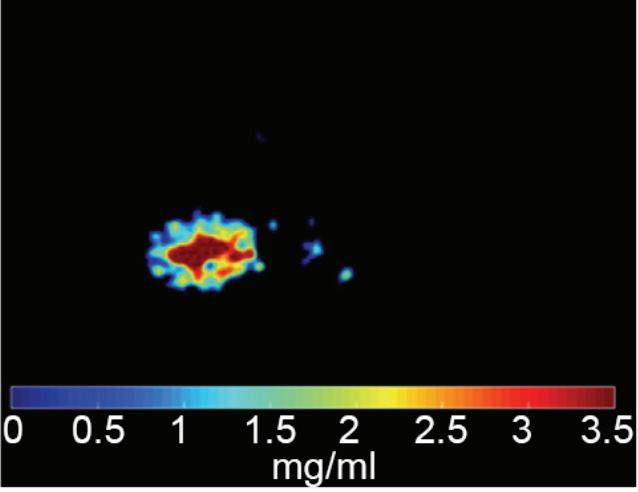

Also referred to as iodine map. This is a quantitative iodine image where voxel values are proportional and scaled to the iodine true concentration in units of mg/ml. Voxels without iodine content have zero iodine and hence are black (Figure 3).

Note: The algorithm includes a low bone removal threshold. Voxels with Ca content below the threshold are classified as containing iodine. The accuracy measured on a Gammex phantom with various concentrations of iodine (up to 20 mg/ml) show an iodine quantification to within 0.3 mg/ml, for both the Iodine no Water and iodine density measurements.21 In clinical conditions, an iodine concentration measurement of 0.5 mg/ml should be considered as the lower threshold for iodine uptake.